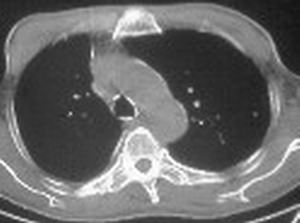

1:右侧结核性胸膜炎,胸腔积液;

2:不排除右肺癌。

影像特征很象,包裹性胸腔积液,建议楼主测ct值鉴别.

右肺下叶支气管闭塞,伴下叶实变不张。建议增强及纤支镜。

右肺下野后部均匀低密度影,边缘锐利,前缘外突(不支持肺不张),纵隔内未见明显肿大淋巴结,右下肺门结构显示欠清,临床资料太过简单,考虑右侧后胸部包裹性积液。其他待排。建议密切结合临床其他检查。